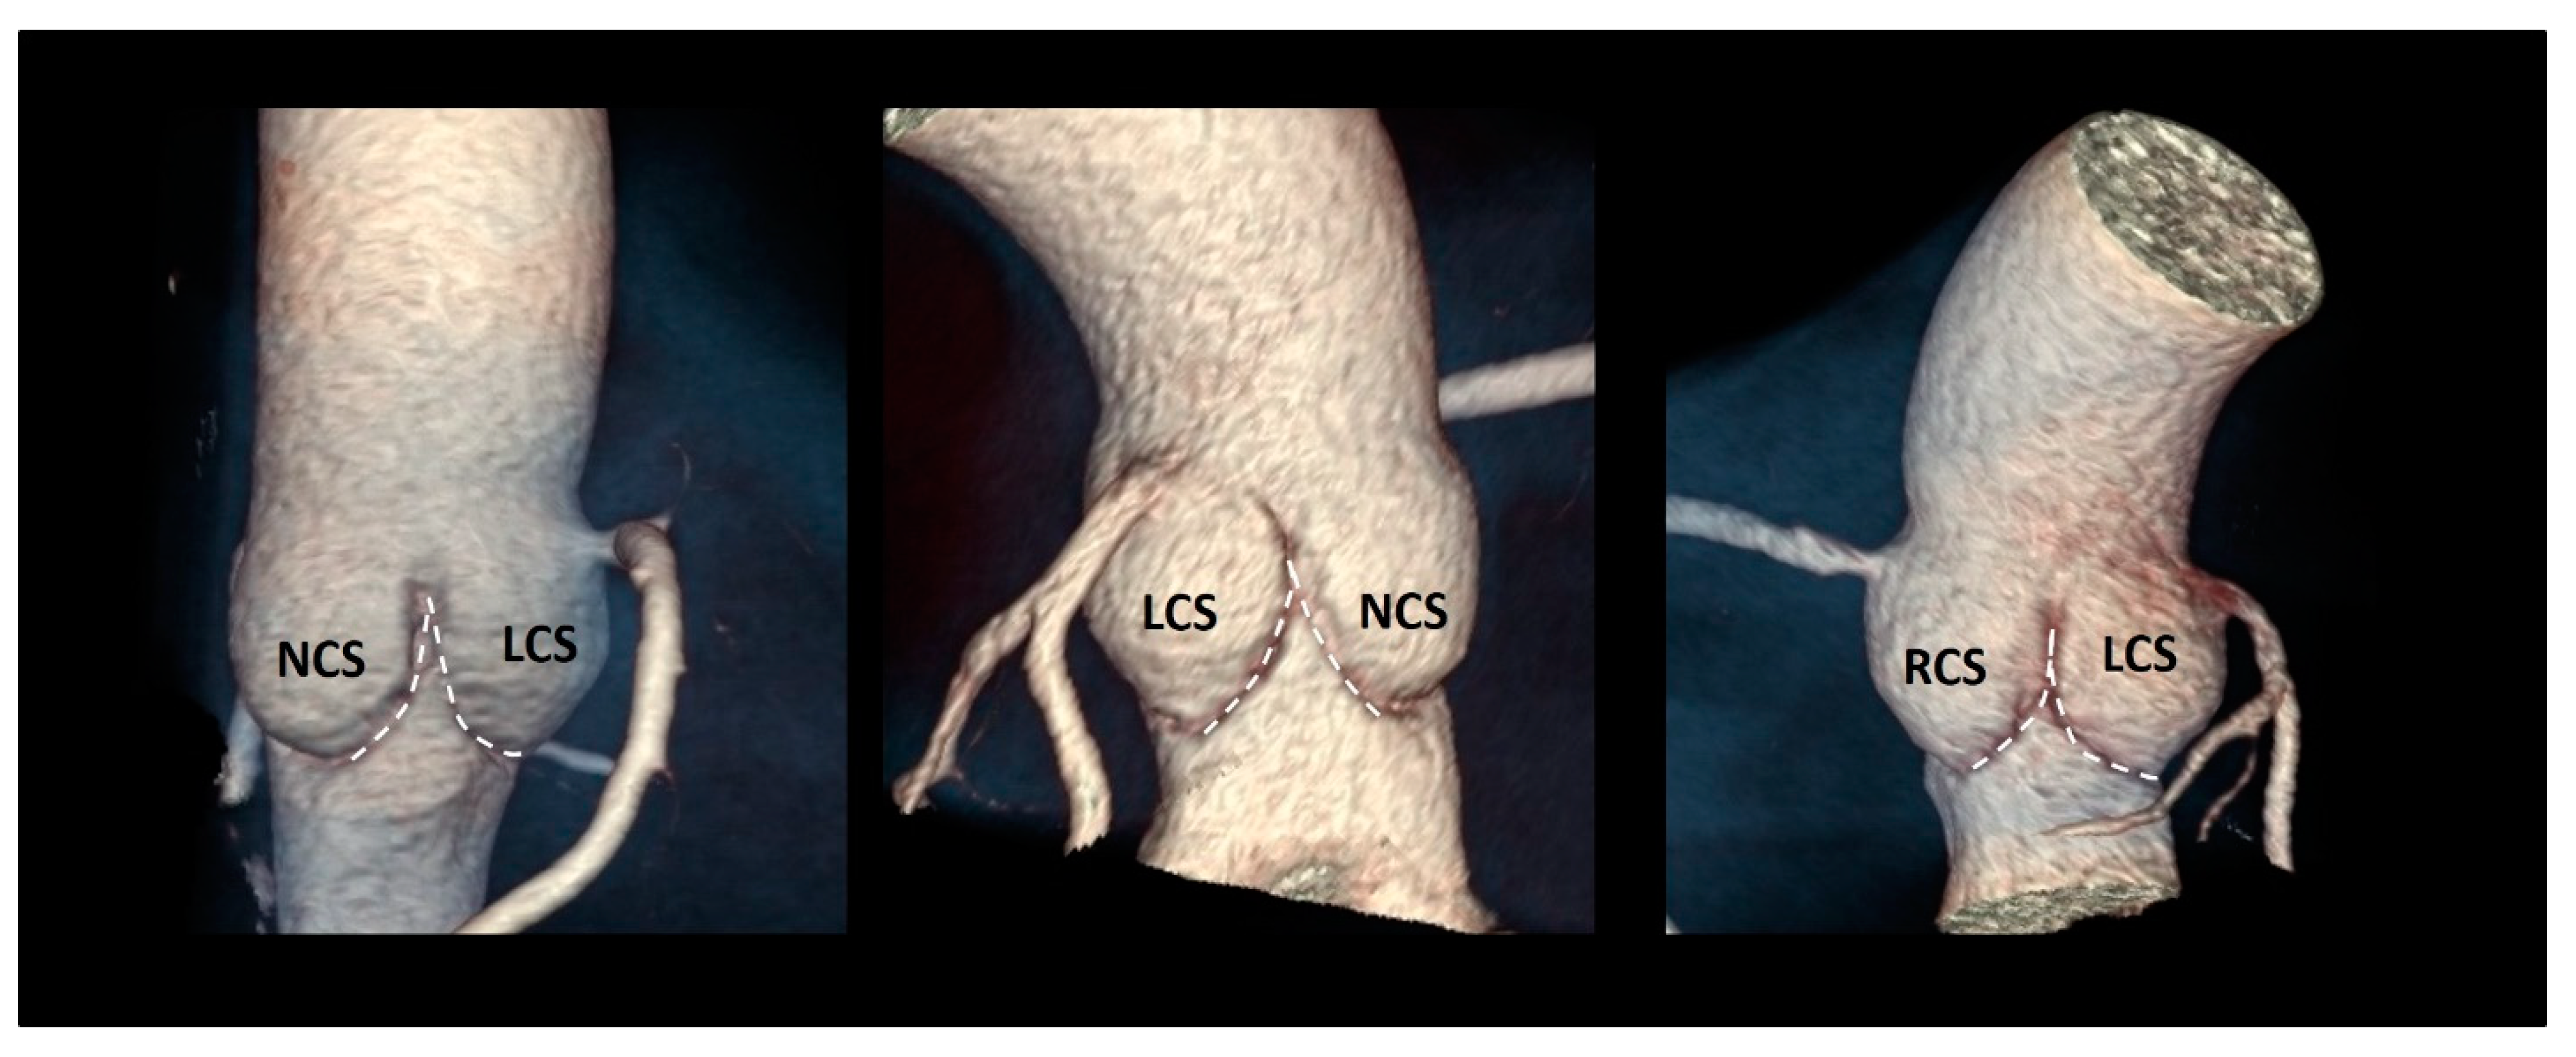

3.10. The Coronary Ostia